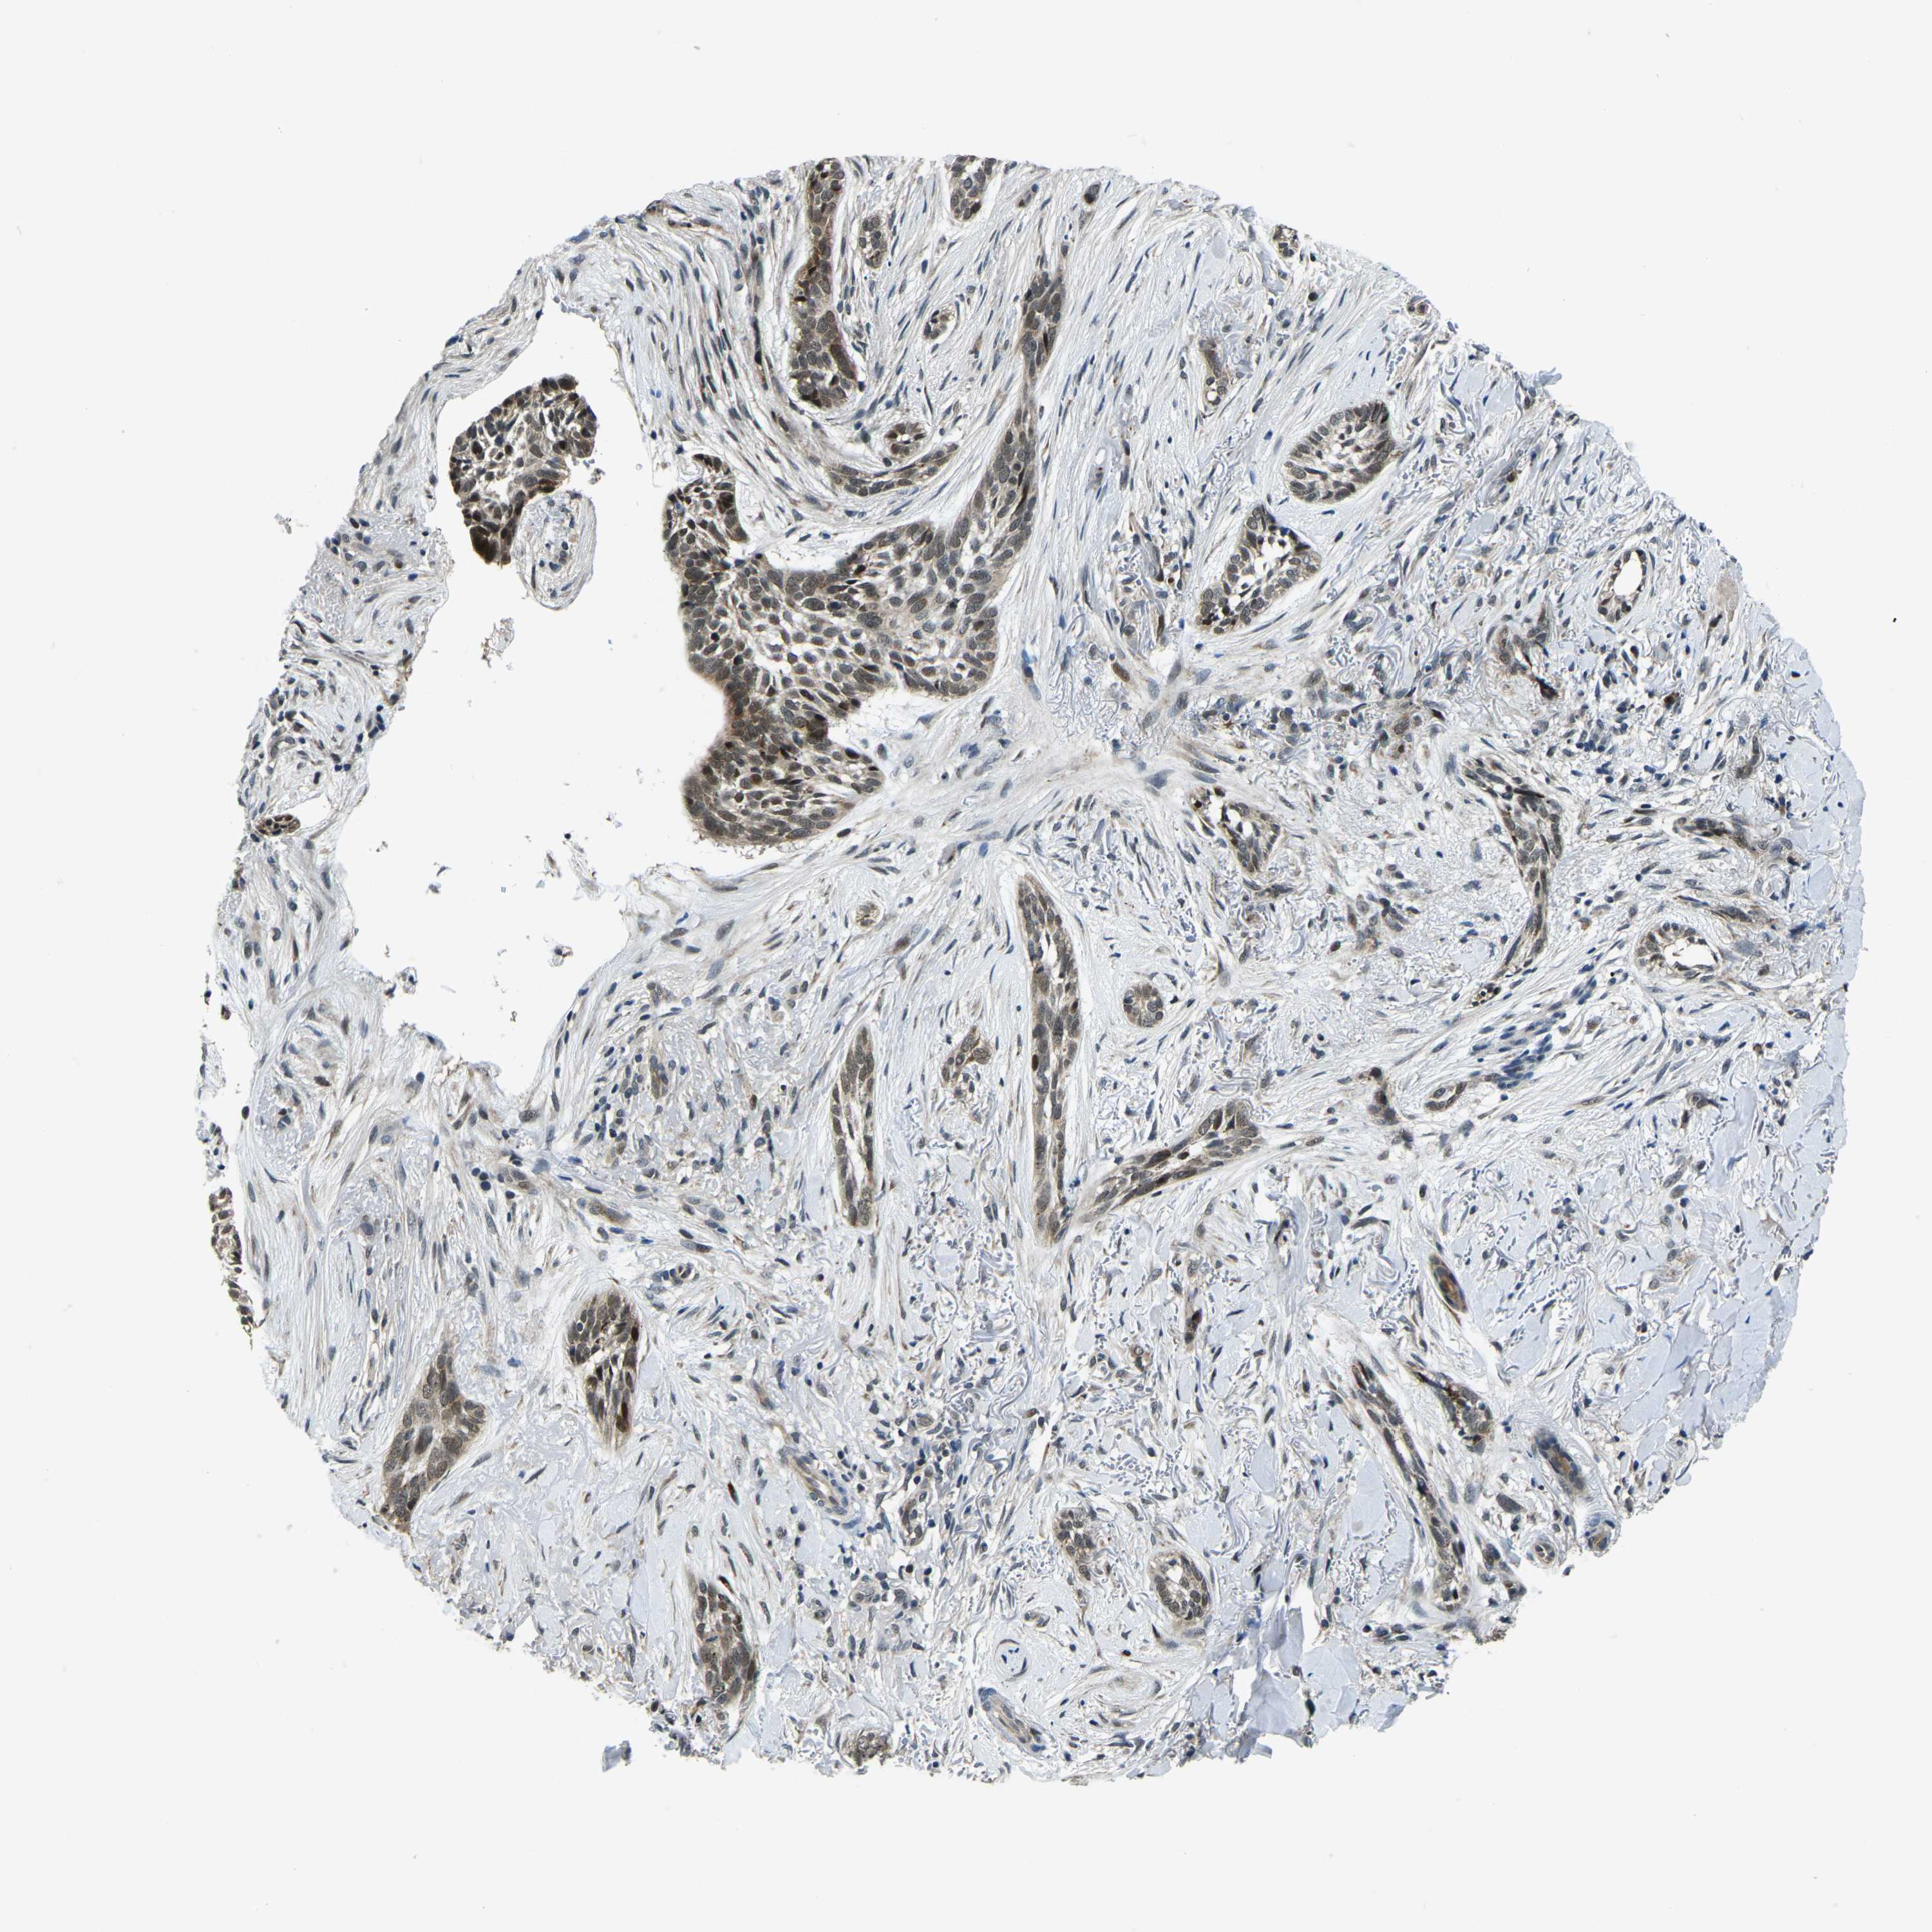

SKIN CANCER - Protein expressioni

A mouse-over function shows sample information and annotation data. Click on an image to view it in a full screen mode. Samples can be filtered based on level of antibody staining by selecting one or several of the following categories: high, medium, low and not detected. The assay and annotation is described here.

Each image is clickable and will lead to virtual microscopy that enables deeper exploration of all samples and also displays staining intensity scores, fraction scores and subcellular localization as well as patient and tissue information for each sample.

Antibody HPA021517

Staining

Medium

Intensity

Moderate

Quantity

75%-25%

Location

Cytoplasmic/membranous

Squamous cell carcinoma, NOS